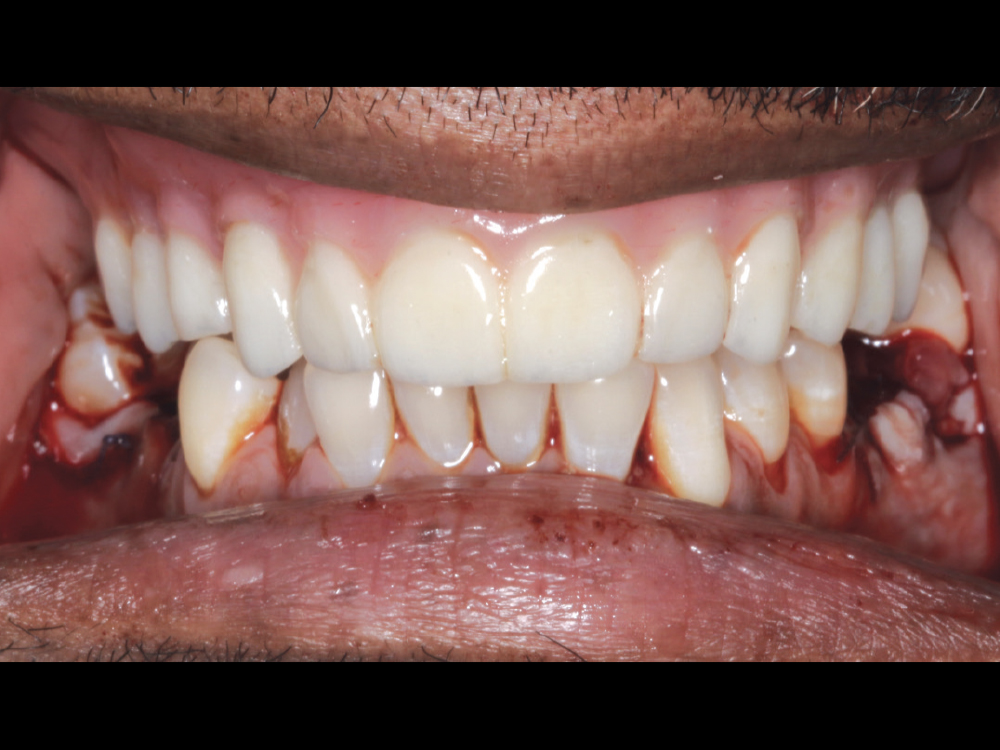

Once the first denture setups were tried in over the multi-unit abutments and approved, a polymethyl methacrylate (PMMA) provisional was milled. I then inserted this prosthesis and verified esthetics and function.

Figures 12a–12c: Once the first denture setups were tried in over the multi-unit abutments and approved, a polymethyl methacrylate (PMMA) provisional was milled. I then inserted this prosthesis and verified esthetics and function.

No changes to the design were indicated, so the final BruxZir Implant Prosthesis was delivered during the next visit. Final adjustments were made, and the screw access holes were sealed with Teflon tape and composite.

Figure 13: No changes to the design were indicated, so the final BruxZir Implant Prosthesis was delivered during the next visit.  Final adjustments were made, and the screw access holes were sealed with Teflon tape and composite.